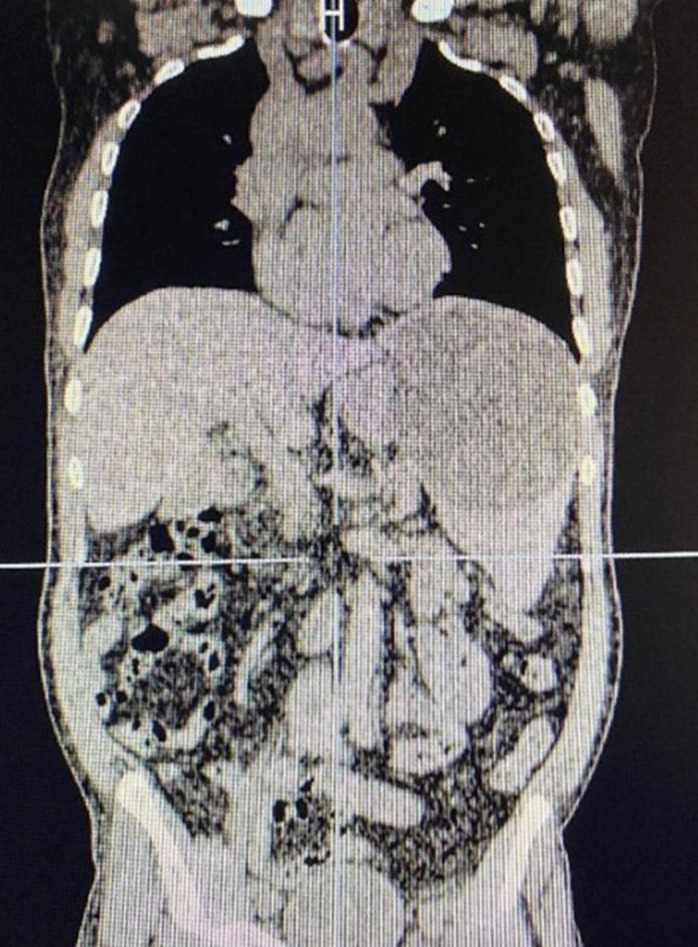

Background & objective: This study presents a rare case of hydatid cysts involving the liver, spleen, and peritoneum, in which clinical features and radiologic findings initially raised strong suspicion for abdominal malignancy with peritoneal seeding.

Case presentation: A 64-year-old man presented with vague epigastric pain, weight loss, and iron deficiency anemia. Abdominal ultrasonography revealed multiple splenic lesions suggestive of hydatid cysts. Hydatid serology was negative. Chest CT was unremarkable. Abdominal and pelvic CT showed splenomegaly with cystic lesions, including a calcified cyst in segment VI of the liver. Numerous hypodense peritoneal nodules were identified, particularly in the mid-omentum and supraumbilical region. Differential diagnoses included hydatid disease, primary peritoneal neoplasms, and peritoneal metastases. Due to anemia, weight loss, and the suspicion of peritoneal carcinomatosis, hydatid disease alone could not fully account for the findings, prompting further diagnostic evaluation. Endoscopy and colonoscopy were unremarkable. The patient underwent exploratory laparotomy and splenectomy, along with partial omentectomy where hydatid involvement was suspected. Postoperatively, he was treated with albendazole 800 mg daily and discharged on postoperative day three. At 3- and 6-month follow-ups, the patient reported resolution of abdominal pain, and physical examinations were normal.

Conclusion: Peritoneal hydatid disease is rare and can mimic peritoneal carcinomatosis, leading to diagnostic uncertainty and treatment delay. Surgical excision followed by antiparasitic therapy remains the cornerstone of management.